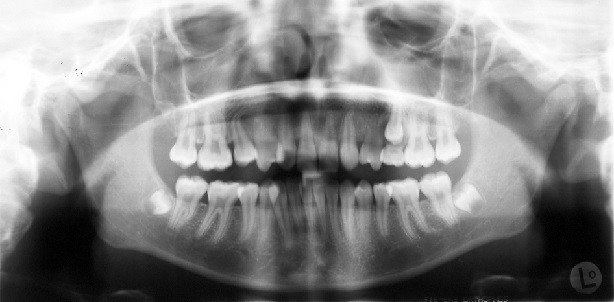

Das angefertigte OPG zeigt (Abb. 4), dass mit Ausnahme der seitlichen Schneidezähne alle Zähne vorhanden waren. Sowohl endodontische als auch konservierende bzw. prothetische Versorgungen waren nicht zu verzeichnen. Die parodontale Situation war röntgenologisch unauffällig und die Knochenverhältnisse ließen eine orthodontische Behandlung zu.

Das OPG zeigt keine Auffälligkeiten, Wurzelresorptionen waren nicht zu verzeichnen (Abb. 9). Zur Verbesserung der dentofazialen Ästhetik im Frontzahnbereich wurde die Form der Eckzähne zu lateralen Schneidezähnen mit Kompositmaterial geändert (Abb. 10a–e, Abb. 11a–c). Zur Retention wurde im Unterkiefer von Eckzahn zu Eckzahn ein Retainer fixiert. Zusätzlich wurden in Ober- und Unterkiefer Retentionsplatten eingesetzt.